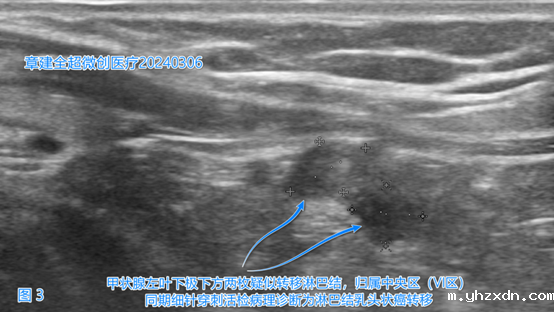

左侧颈部IIA(2A)区(图3)、

右侧颈部VI(6)、右侧颈部VII(7)区(图5)出现了疑似癌转移的淋巴结。